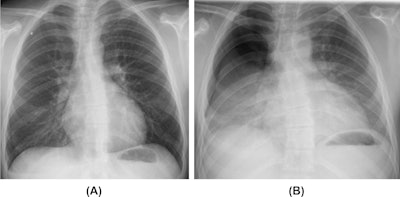

Barotrauma in a cannabis smoker. A 21-year-old man who is a habitual cannabis smoker presented to the emergency department with right-sided sudden chest pain and dyspnoea. (A) Inspiratory posteroanterior chest radiograph reveals a small right superior pneumothorax. (B) Expiratory posteroanterior chest radiograph better demonstrates the right-sided pneumothorax.